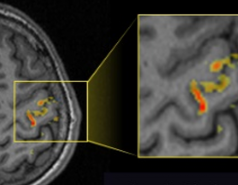

High-resolution functional MRI